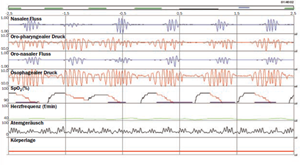

Der Apneagraph ist ein modernes Diagnostikverfahren und lokalisiert die Engstelle.

Es ist ein neues, innovatives diagnostisches Instrument zur sicheren Erfassung der Atmungsanstrengungen. Der Atemfluss und die korrespondierende Atmungsanstrengung werden kontinuierlich an jeweils zwei Orten der oberen Atemwege erfasst.

Dies ermöglicht eine genaue Ortung der schlafbezogenen Obstruktionen (Apnoen, Hypopnoen und Schnarchen) sowie eine Differenzierung von zentralen Atmungsstörungen.